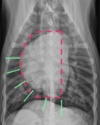

Which structures pair with the times on the “clock face” of the heart in a VD view?

11:00 to 1:00: aortic arch

1:00 to 2:00: main pulmonary artery segment

2:30 to 3:00: left auricle

3:00 to 5:00: left ventricle

5:00 to 9:00: right ventricle

9:00 to 11:00: right atrium

9

What is indicated by the white circle in this image?

A

position of the left atrium

-does not contribute to “clock face”

-between the main stem bronchi